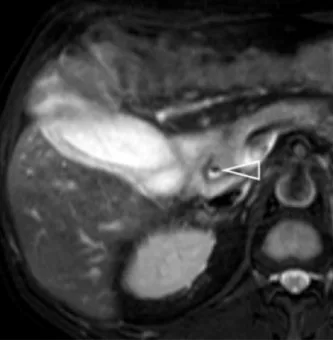

A

B

Figure 10.

A. Mise en évidence de lithiases intrahépatiques en bili-IRM.

B. L’échographie est un complément utile, car la bili-IRM peut avoir du mal à détecter les calculs quand les voies biliaires sont

de petit calibre. Ici l’échographie montre la présence de dépôts de cholestérol le long de petites voies biliaires intrahépatiques, visibles

sous la forme d’une image en « queue de comète », classique mais dont la recherche nécessite une exploration ciblée attentive. Devant des antécédents de cholestase gravidique et de symptomatologie biliaire avant 40 ans ayant récidivé après cholécystectomie, cette patiente présente avec l’imagerie tous les critères diagnostiques d’un syndrome LPAC. Cette prédisposition à la pathologie biliaire pourra être confirmée par une recherche génétique, et donner lieu à un traitement médical et un dépistage familial